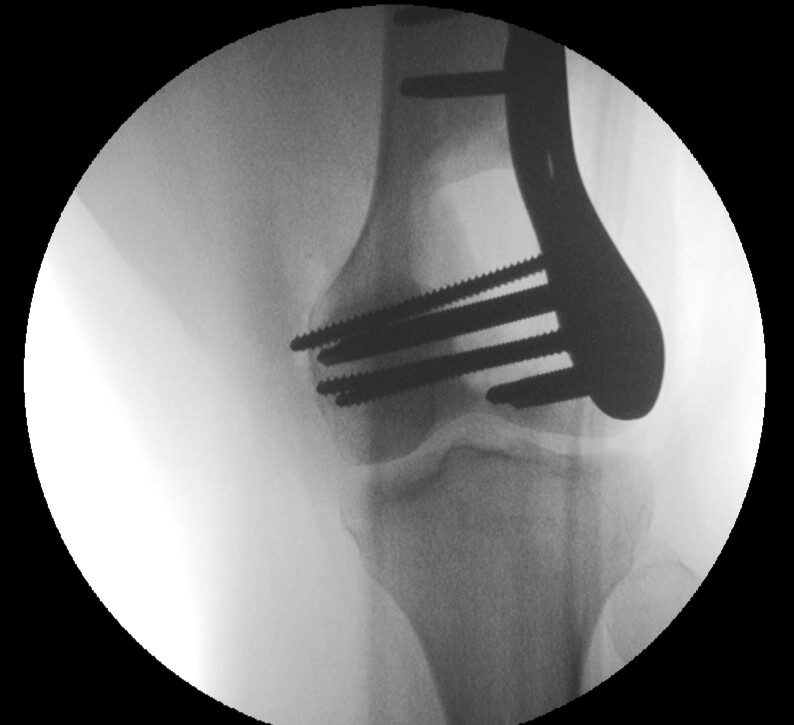

Plain x-ray

• Radiographs of low grade intraosseous osteosarcoma may demonstrate a benign appearance (Fig. 1 & 2).

• However, most lesions show intramedullary extension, cortical violation, and soft tissue involvement.

• The majority arise centrally in the bone, from the medullary cavity and more frequently are methaphyseal.

Fig. 1 & 2: Plain X Ray of Low Grade Intraosseous Osteosarcoma. AP (Fig. 1) and Lateral (Fig. 2) view of the left knee, shows a mixed sclerotic-lytic lesion in the supracondylar area of the femur. There is no periosteal reaction, cortical destruction, or extraosseous soft tissue mass. The lesion is fairly well circumscribed with a sclerotic margin. The lesion deceptively looks benign